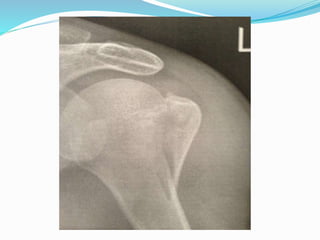

El documento trata sobre la anatomía y la funcionalidad del complejo articular del hombro, enfocándose en espacios quirúrgicos específicos en la región posterior. Se presenta información relevante sobre la cintura escapular y su relación con el hombro. El análisis realizado por el Dr. Luis Francisco Chávez Flor abarca aspectos clave para la comprensión de procedimientos quirúrgicos en esta área.